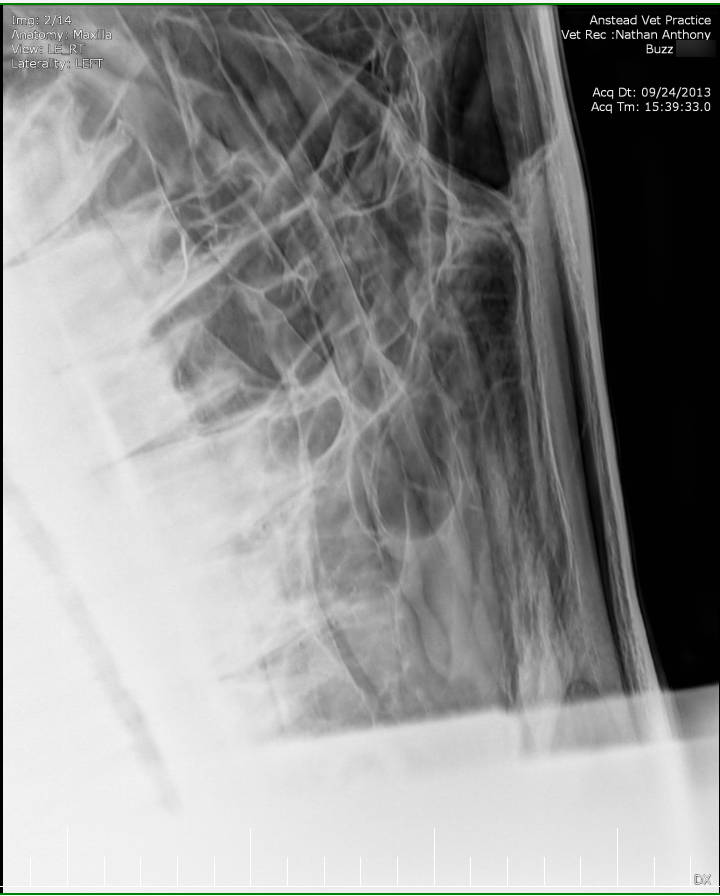

Posted on Sunday, May 8, 2016 - 6:24 pm: Thank you for the welcome!I did contact the lab to see if they still had the samples but they will only speak to the vets who submitted the samples. I've asked my vet to ask on my behalf but haven't yet heard back yet. The horse has been scoped and I was told that it all looked normal. The stylohoid bone and guttural pouches normal. The inflammation is mostly around the nostrils as per the pic but there are a couple of small spots further up inside the nose. He's also had his skull xrayed which I'm told also looked normal. I've included the pics at the bottom. I've included a list of other things here that have been tested to see if they influence the shaking or inflammation for the better or worse: - experimental course of Equity - Flixotide via inhaler - high dose of prednisolone - did work! - low dose of prednisolone - did not work - teeth checked by two different vet dentists - fly masks & nose nets - relocated him to several different places in the city incase it's an environmental allergen - all sorts of feed supplements - removed all hard feed, just feeding hay - stabled him 24/7 and fed him Haygain steamed hay incase it was something in the paddock - light/dark makes no difference to the shaking - it's not seasonal, happens year round I've also had bloodwork done and it showed a low red blood cell count. The blood was taken two weeks after the biopsies. My vet didn't think the low count was attributed to the blood loss from the biopsies so he suggested parasites but a worm count came back clean. I also had a test to see if there was blood in the manure, but nothing was found. There was no plan made to address the low RBC. Results are attached in a text file to maintain the spacing.

Xray images: